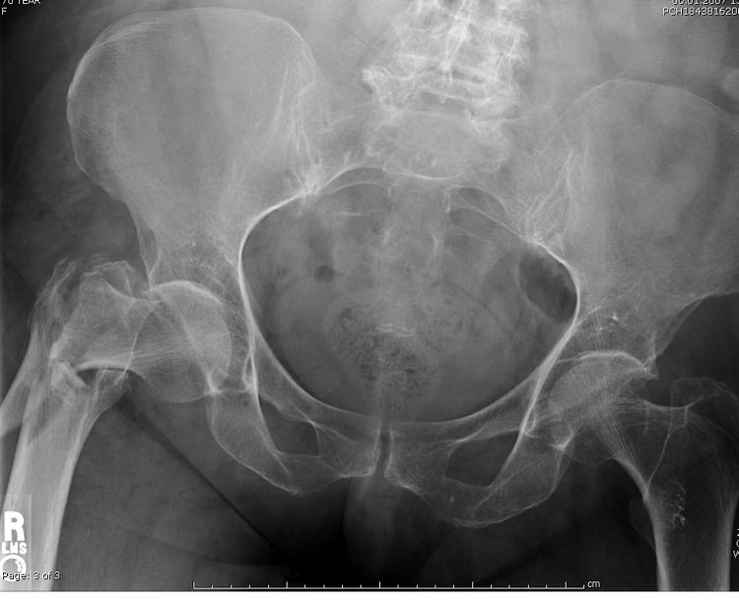

Здесь 83 года, травма в результате падения